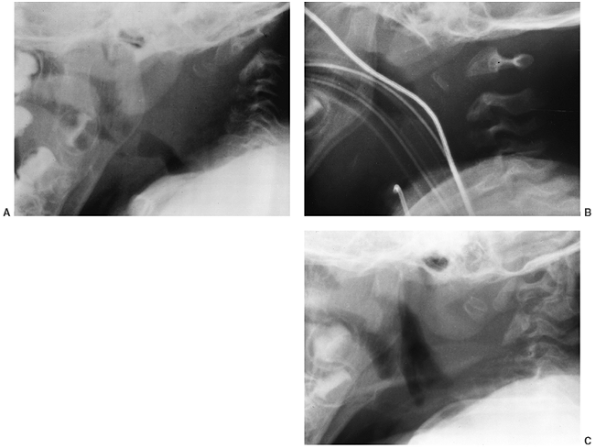

Cervical kyphosis is seen in one third to one half of patients (8,91);

this disorder may be present in infancy, and its course is variable.

Spontaneous resolution has been reported in a number of patients, even

in those with curves of up to 80 degrees (92,93) (Fig. 8.16 A, B). However, other cases progress, and there are several reports of quadriparesis resulting from this deformity (8,94). Scoliosis develops in at least one third of patients (91),

Figure 8.16 Cervical kyphosis in a 1-year-old child (A)

with diastrophic dysplasia is pronounced, with marked deformity of C4. The findings of neurologic examination are normal. Four years later, the condition is markedly improved without any intervention (B), and 7 years later the vertebral bodies have been restored to nearly normal shape, although the canal remains narrow (C). |